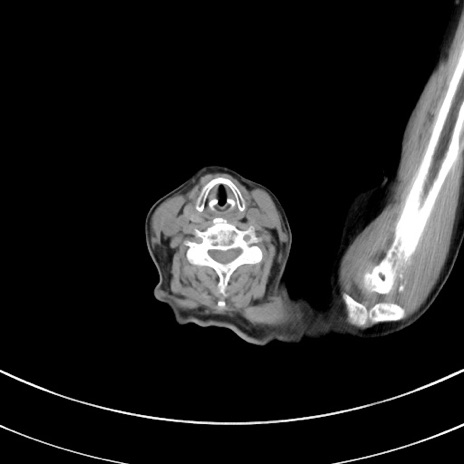

症例33(横断像)

【症例】70歳代 女性

【主訴】心窩部痛

【現病歴】延髄病変の精査・加療にて神経内科入院中。本日より心窩部痛あり。

【既往歴】虫垂炎

【身体所見】右下腹部を中心に圧痛と反跳痛あり。

【データ】WBC 10900、CRP 0.02